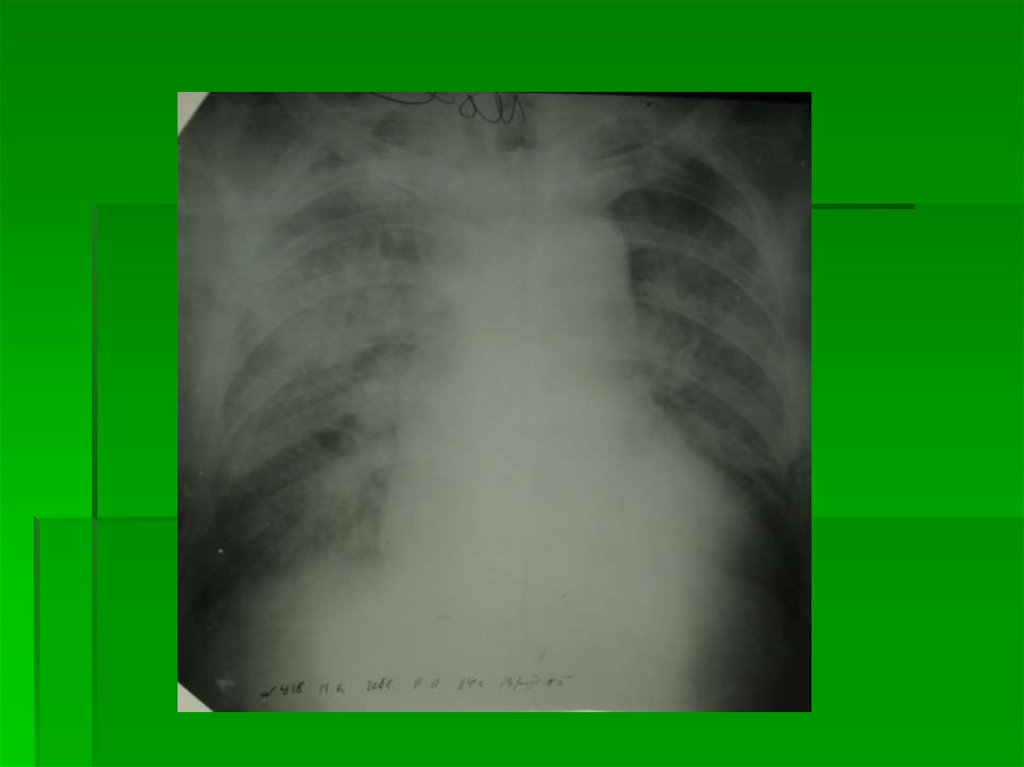

3 степень

Интерстициальный отек

легких

Выход жидкой части крови за пределы

сосудистого русла в интерстициальную

легочную ткань

Корни легких неструктурны,

гомогенизированы, однородны

На фоне корней легких – сосуды в

ортопроекции практически не

дифференцируются

Дифференцируются в ортопроекции

просветы бронхов с утолщенными стенками

в виде маленькой кольцевидной тени с

нечеткими наружными контурами

22.

Прозрачность легких снижена за счет

обилия элементов легочного рисунка

Легочный рисунок утратил обычную

архитектонику, представлен множеством

очаговоподобных теней (расширенные

сосуды в ортопроекции)

и полигональных теней (отечные

междольковые и межальвеолярные

перегородки в ортогональной и косой

проекциях)

23.

Лимфостаз в виде Линий Керли (Kerley) как

обязательный признак ЛВГ 3

Определяются в латерально-базальных

отделах легких (над синусом) в виде коротких

перегородочных линий L=0,5-2,5 см, широким

основанием прилежащих к грудной стенке

Нежная «волосяная» тень междолевой

плевры (лимфостаз по ходу плевры)